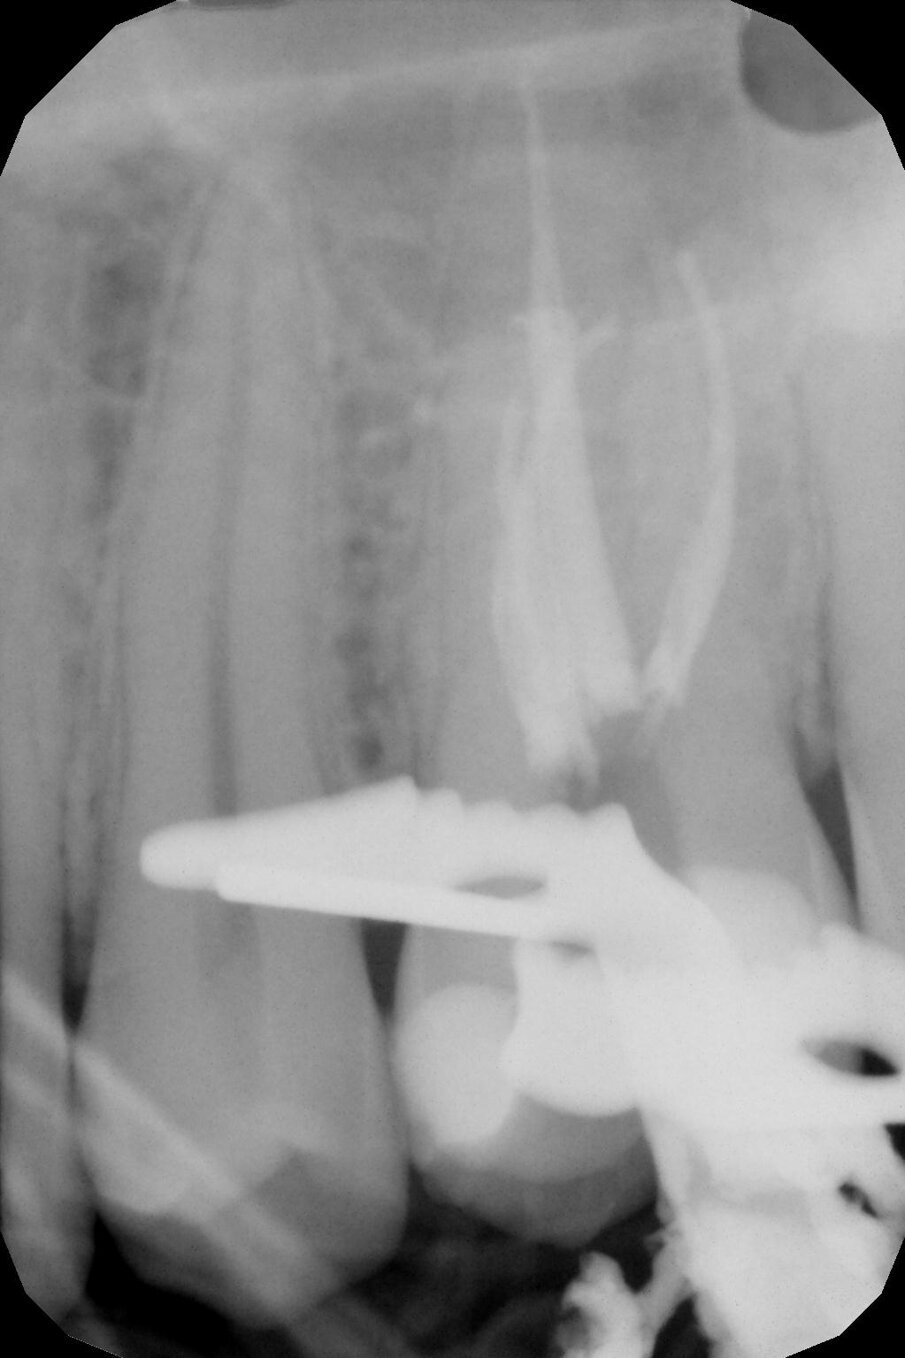

Si completa la preparazione canalare con 20.05, 25.04 e 30.04 VDW.Rotate (Dentsply Sirona) per i canali MV, Mb2 e DV, mentre per il canale palatale si è scelta una preparazione 40.04 (Fig. 2).

La tecnica di sagomatura canalare è una preparazione simultanea, dove al classico movimento di Up & Down si associa il nuovo movimento di micro-pecking. Gli strumenti, passati in sequenza dal più piccolo al più grande, vengono fatti lavorare con un movimento di spazzolamento associato a uno di picchiettio possibile grazie all’aumento del tempo di latenza con cui si lavora con la punta dello strumento all’interno del canale. Ciò è realizzabile grazie al disegno e alla lega con cui sono realizzati i Rotate. La rifinitura apicale, usando la tecnica del visual gauging, è stata affidata a strumenti meccanici rotanti 35.04 e 40.04 VDW.Rotate (Dentsply Sirona) nel canale P, mentre al 30.04 VDW.Rotate (Dentsply Sirona) nei canali MV, Mb2 e DV.

La chiusura canalare è stata eseguita con tecnica Micro-Heat: termomeccanica laterale a caldo (Mul-ti-Phase di McSpadden), con cono master di diametro #40 e conicità 02 nel canale palatale P (ldl: 22mm) e #30 conicità 0.2 nei canali MV (ldl: 20mm), Mb2 (ldl: 20mm) e DV (l.d.l: 20 mm), associato a cemento endodontico a base di ossido di zinco eugenolo con sali d’argento (Pulp canal sealer, Kerr); il Back-Packing è stato eseguito con Pac-Mac Sybron-Endo Microseal Condenser, Pac-Mac (Kerr) e guttaperca fluida Microseal (Sweden&Martina) (Fig. 4).

Fig. 2 - Sequenza degli strumenti meccanici usati per la preparazione canalare: Tecnica simultanea.

Fig.4 - Rx-periapicale di controllo post-operatoria.